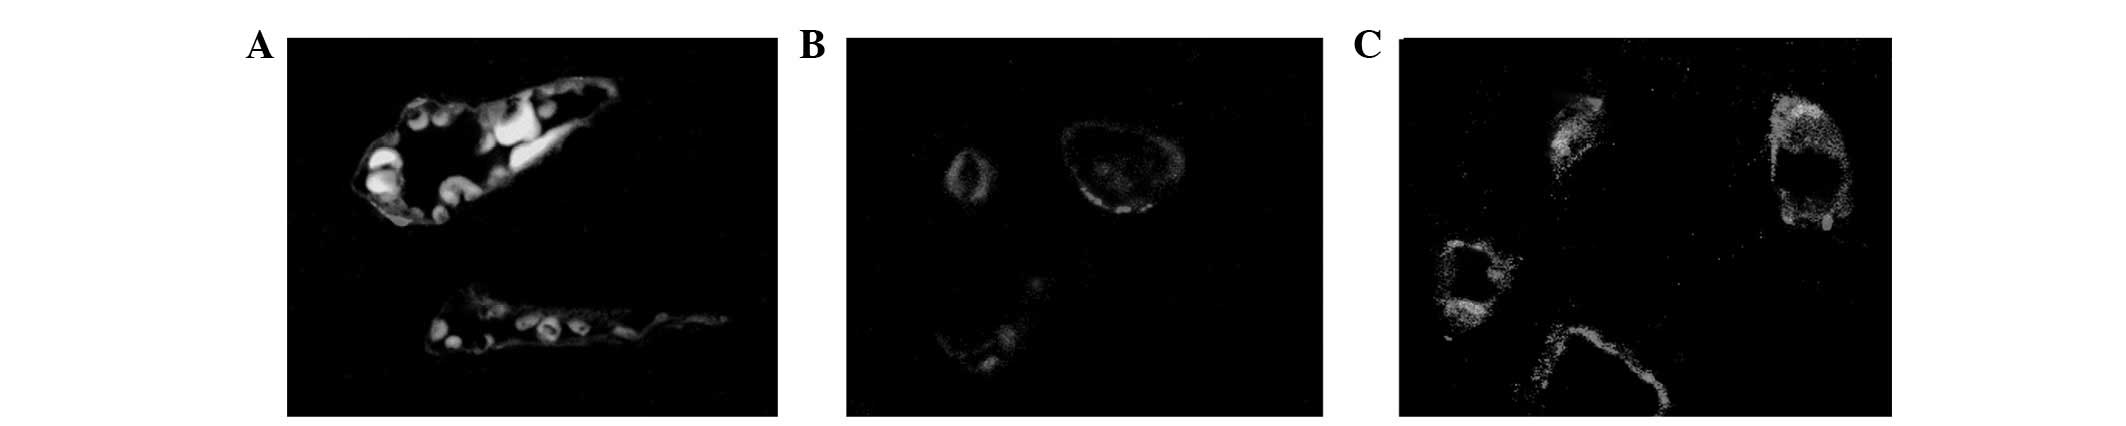

Immunofluorescence of CD31 expression

As shown in Fig. 6, CD31 was highly specific and sensitive for vascular endotheliocytes. Fibrosis triggered the CD31 expression of endotheliocytes.

Figure 6

CD31 staining of myocardial tissue in rats. (magnification, ×400). (A) Control group; (B) 2 h after ISO injection; (C) 21 days after ISO injection. ISO, isoprenaline hydrochloride.